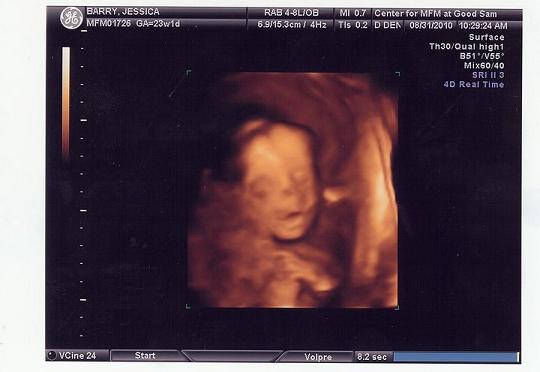

I went to the high risk ob at good sam for an apt today at 23w1d

Baby is measuring a pound and a half, femurs are on track, pinky fingers are perfect, and everything is perfect.

After all the worry and the scares the dr said baby is perfect and we got really good 3d pics but these are just a picture of the pictures so they might not be that clear.

Image Attachment(s):